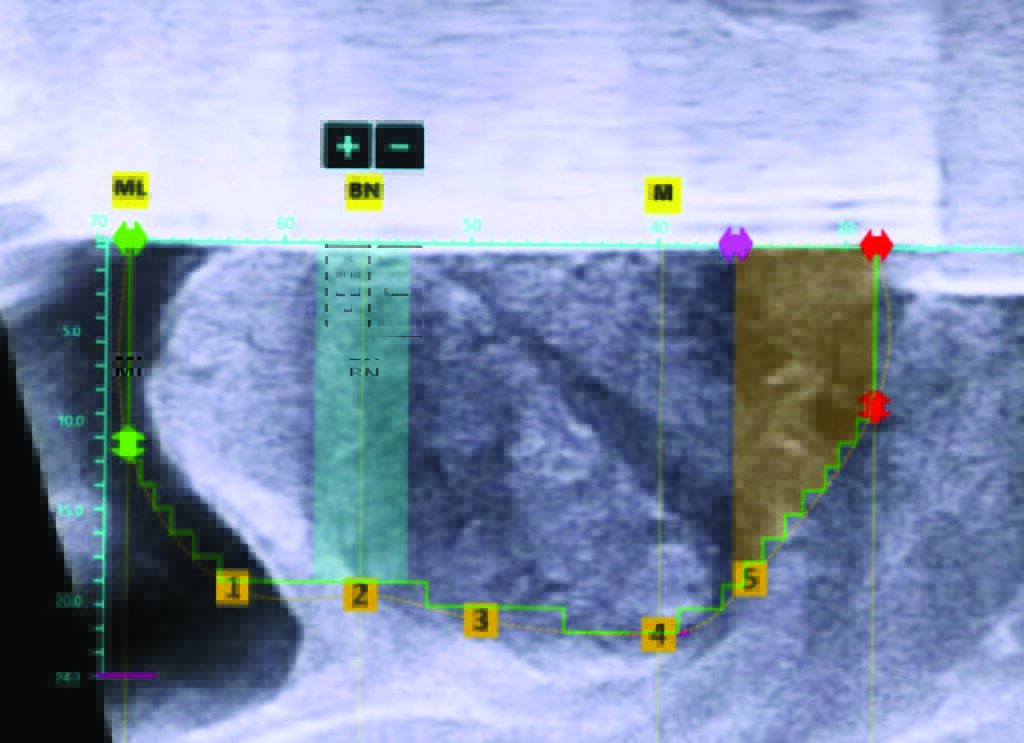

Personalized treatment planning

Computer-assisted planning allows the surgeon to maximize tissue resection while sparing the bladder neck, verumontanum, and external sphincter.

Robotic-assisted waterjet resection

Robotic-assisted resection delivers predictable execution in prostates of all shapes and sizes with heat-free waterjet resection.